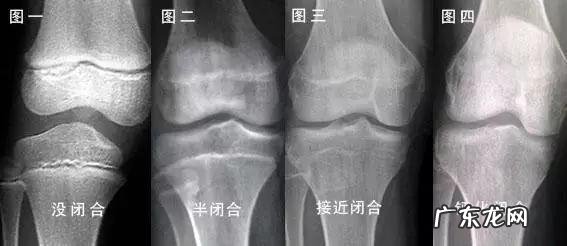

孩子能不能长高,有一个直观的方法——拍个x光片看看下肢长骨的骨骺是否闭合 。

见下图↓

如果骺板(也叫生长板)x光片看起来是透明的区线,那么OK!孩子长高的空间很大 。

如果骺板与相邻的骨骺融合一体了,那么就非常遗憾,吃啥都没用,更别说按摩了!

所以身高增长与年龄没有太大关系,很多人成年之后还会长高,这是因为ta的骨骺没有闭合 。闭合了,无论你年龄多小都没戏!